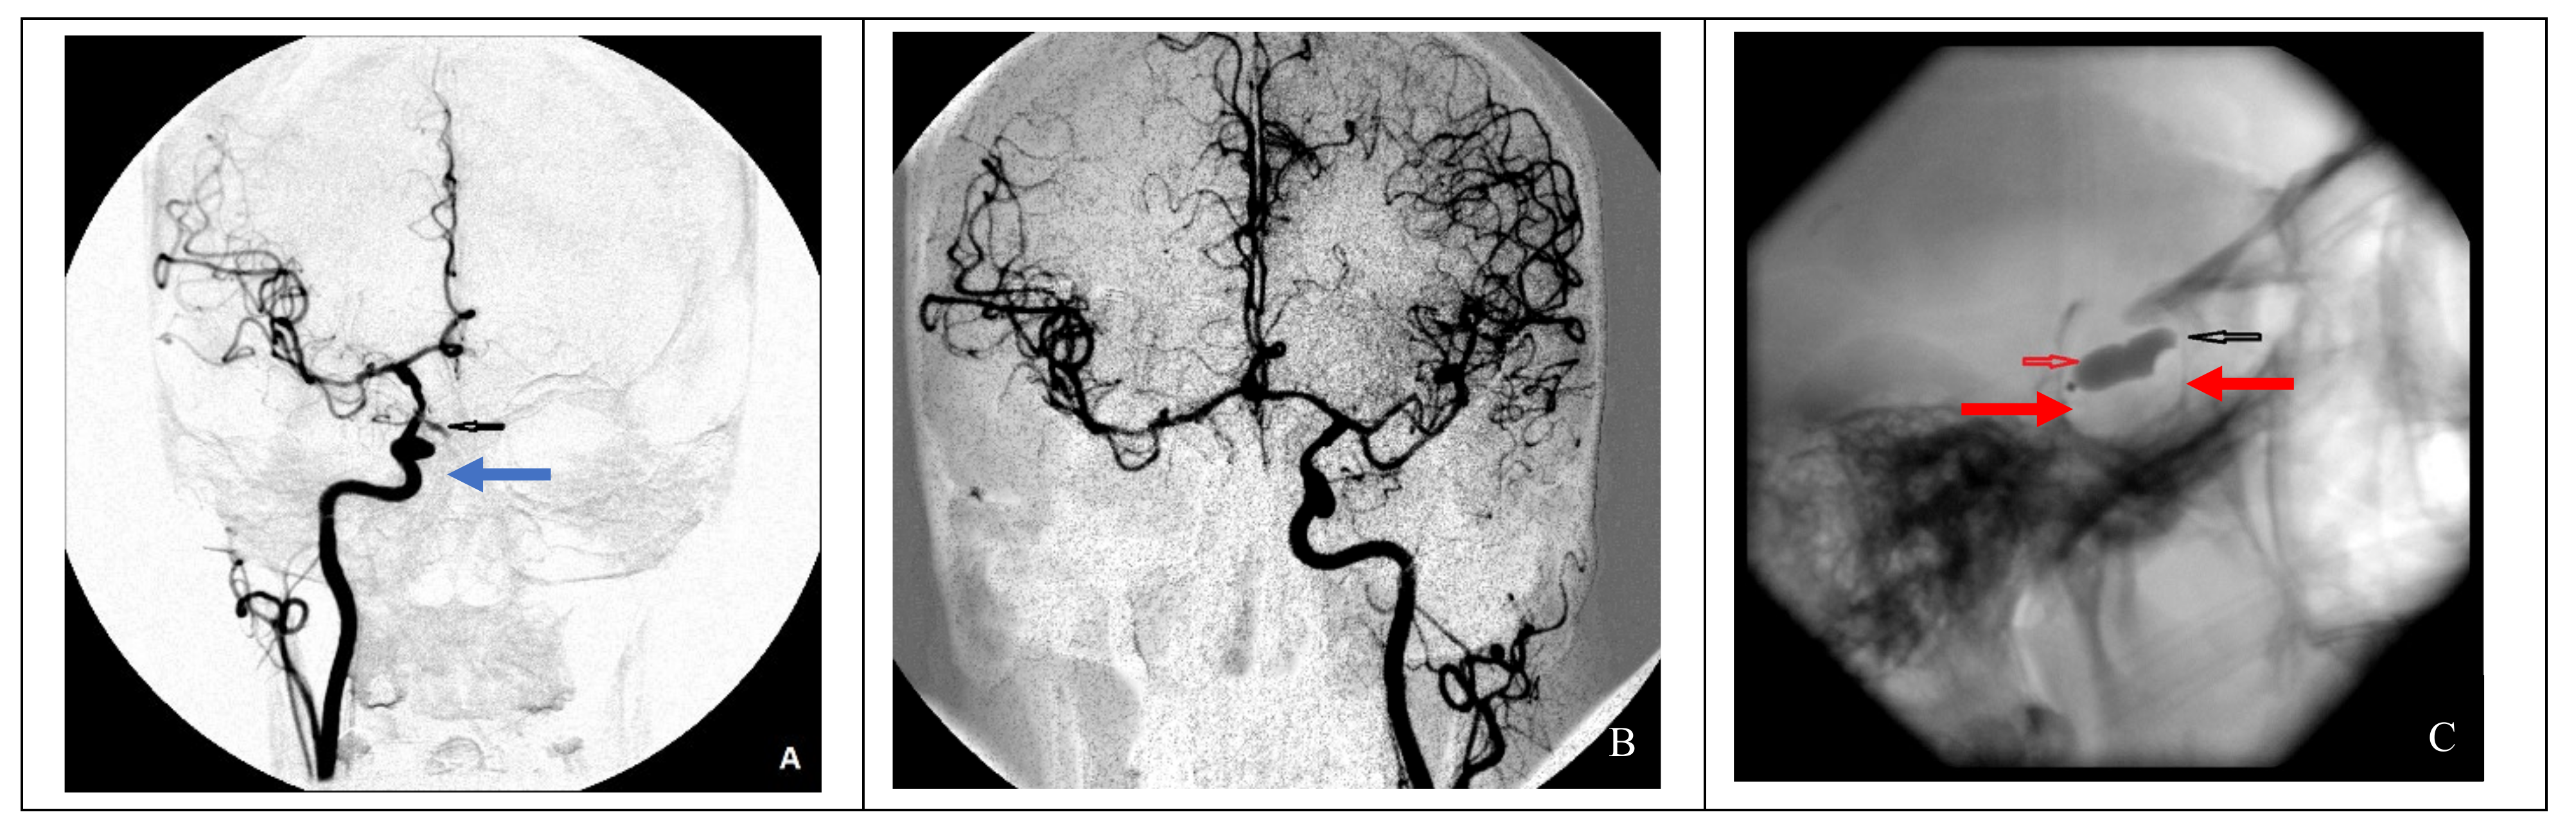

In the case of nonsufficient collateral circulation, the approach to closing the defect required maintaining the blood flow in the basin of the injured artery (reconstructive surgery) or replacing the blood flow (bypass) in the MCA basin on the ipsilateral side: in one case, the patient underwent a stent-graft procedure (Figure 4), and one patient underwent a high-flow bypass followed by ICA occlusion using microcoils (Figure 5).

Figure 4. Endovascular treatment in a case of nonsufficient circulation (clinical case 4). (A) Formation of a false aneurysm at the level of the cavernous segment of the right ICA (blue arrow), (B) cerebral angiography of the left ICA indicating nonsufficient collateral circulation on the right side, and (C) installation of a stent graft (red arrow) at the site of the right ICA injury.